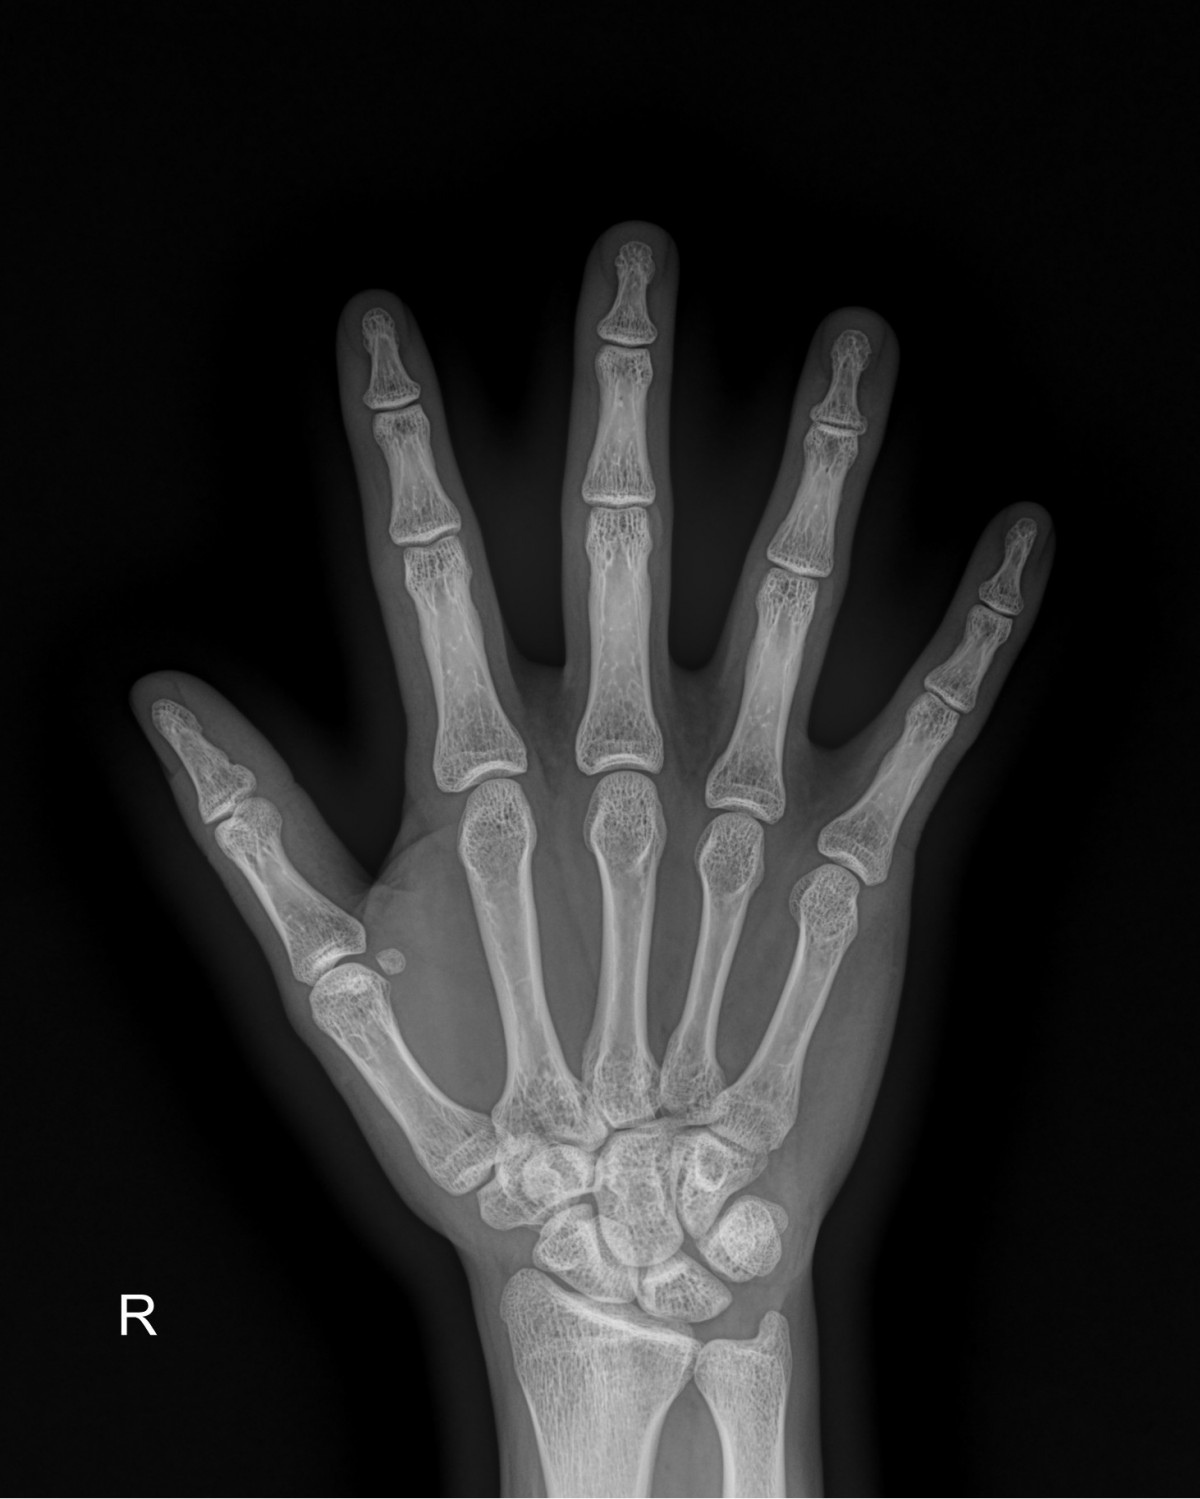

정지영원장님 손가락 골절 수술 안기O 환자

dae765e4d9ac96aee867c9d6292d8784_1758008489_6237.jpg